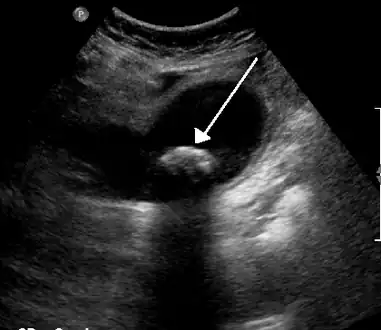

Diagnosis is typically confirmed by abdominal ultrasound. Other imaging techniques used are ERCP and MRCP. Gallstone complications may be detected on blood tests.[2]

On abdominal ultrasound, sinking gallstones usually have posterior acoustic shadowing. In floating gallstones, reverberation echoes (or comet-tail artifact) is seen instead in a clinical condition called adenomyomatosis. Another sign is wall-echo-shadow (WES) triad (or double-arc shadow) which is also characteristic of gallstones.[38]

A 1.9 cm gallstone impacted in the neck of the gallbladder and leading to cholecystitis as seen on ultrasound. There is 4 mm gall bladder wall thickening.

Biliary sludge and gallstones. There is borderline thickening of the gallbladder wall.